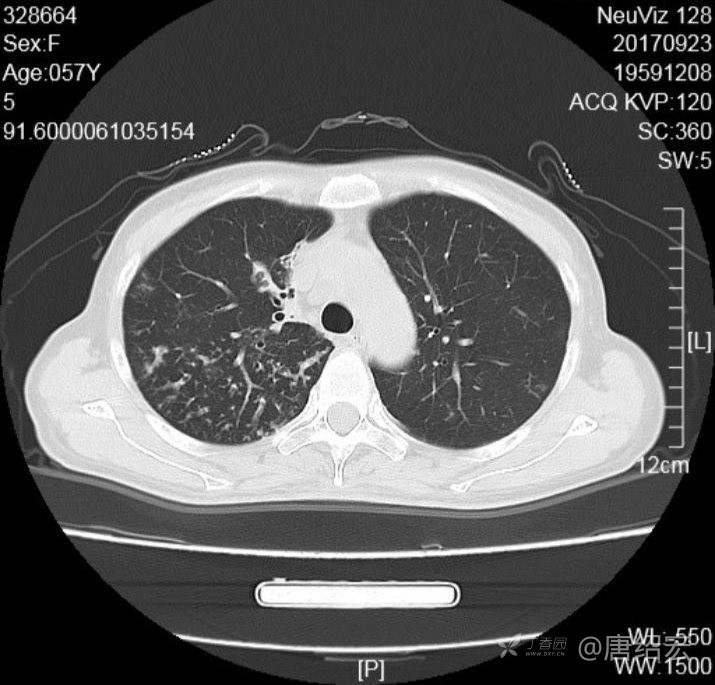

女,57岁,

主诉:发热、咳嗽、咯黄痰,胸闷3天入院。

铜绿假单胞菌性肺炎 (12)

铜绿假单胞菌感染 (20)